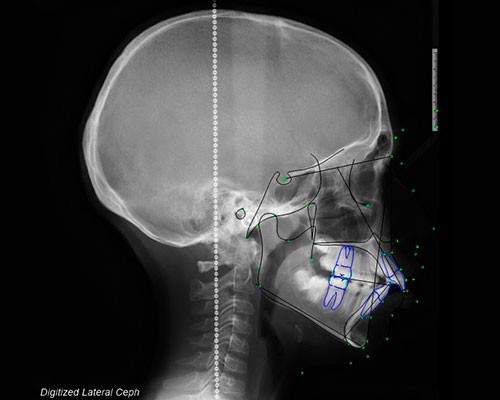

SISTEMAS DIGITALES 3D